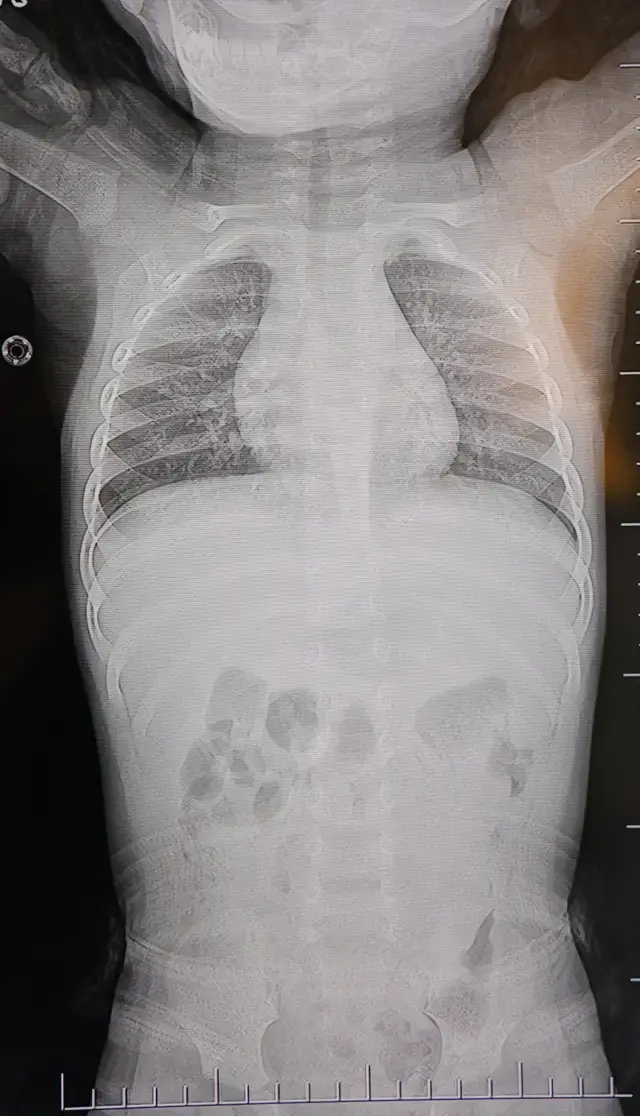

Yapılan görüntüleme yöntemleri sonucunda, bebeğin sırtında cilt altında bulunan metal bir cismin omurilik kanalına çok yakın bir noktada olduğu belirlendi. En dikkat çekici bulgu ise cismin, akciğer zarına doğru ilerliyor olmasıydı. Uzmanlar, bu konumun son derece riskli olduğuna dikkat çekerek acil müdahale kararı aldı. Yabancı cismin yer değiştirmesi durumunda hayati organlara zarar verme ihtimali olduğu vurgulandı.

Bebek, genel anesteziye alınmadan lokal anestezi ve sedasyon eşliğinde ameliyata alındı. Gerçekleştirilen cerrahi müdahalede yabancı cisim tamamen çıkarıldı. Yapılan incelemede cismin, ince zımba teline benzer metal bir tel olduğu ve yaklaşık 2 santimetre uzunluğunda bulunduğu tespit edildi. Operasyonun başarılı geçmesinin ardından bebeğin genel durumunun iyi olduğu bildirildi ve aynı gün taburcu edildi.